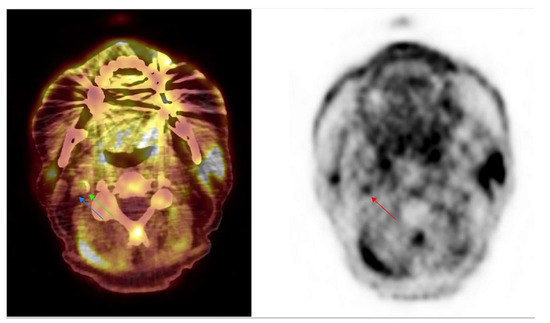

[18F]FDG PET/CT Imaging in Large Vessel Vasculitis